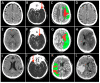

The approach to reperfusion therapies in stroke patients is rapidly evolving, but there is still no explanation why a substantial proportion of patients have a poor clinical prognosis despite successful flow restoration. This issue of futile recanalization is explained here by three clinical cases, which, despite complete recanalization, have very different outcomes. Preclinical research is particularly suited to characterize the highly dynamic changes in acute ischemic stroke and identify potential treatment targets useful for clinical translation. This review surveys the efforts taken so far to achieve mouse models capable of investigating the neurovascular underpinnings of futile recanalization. We highlight the translational potential of targeting tissue reperfusion in fully recanalized mouse models and of investigating the underlying pathophysiological mechanisms from subcellular to tissue scale. We suggest that stroke preclinical research should increasingly drive forward a continuous and circular dialogue with clinical research. When the preclinical and the clinical stroke research are consistent, translational success will follow.